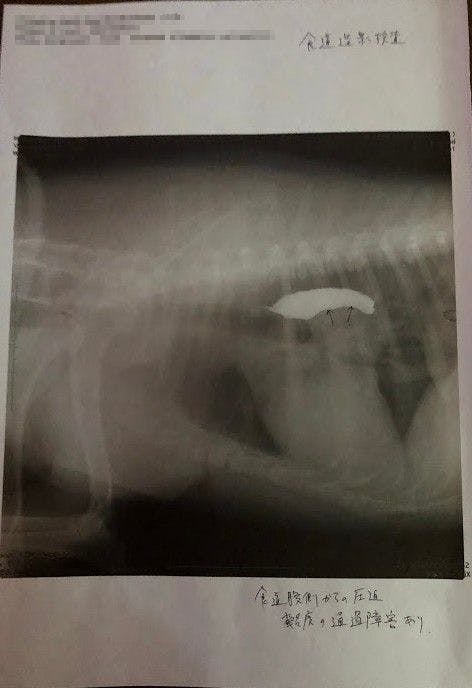

↑

バリウム飲んで検査してもらったところ、矢印の部分に腫瘍があり(白い部分は食道)、それが食道を押し上げているため、飲んだ水を吐いたりするとのことでした。(この時点で5センチほどの大きさの腫瘍でした。)

↑腫瘍の場所が体の奥のにある為、CT検査できる大学病院で検査してから手術するかどうか決めたほうがいいと言われました。

これだけだとよくわからないと思うので、昨年末に撮ったレントゲン写真と並べてみました。

腫瘍の大きさが2倍以上になっていたのです(泣)